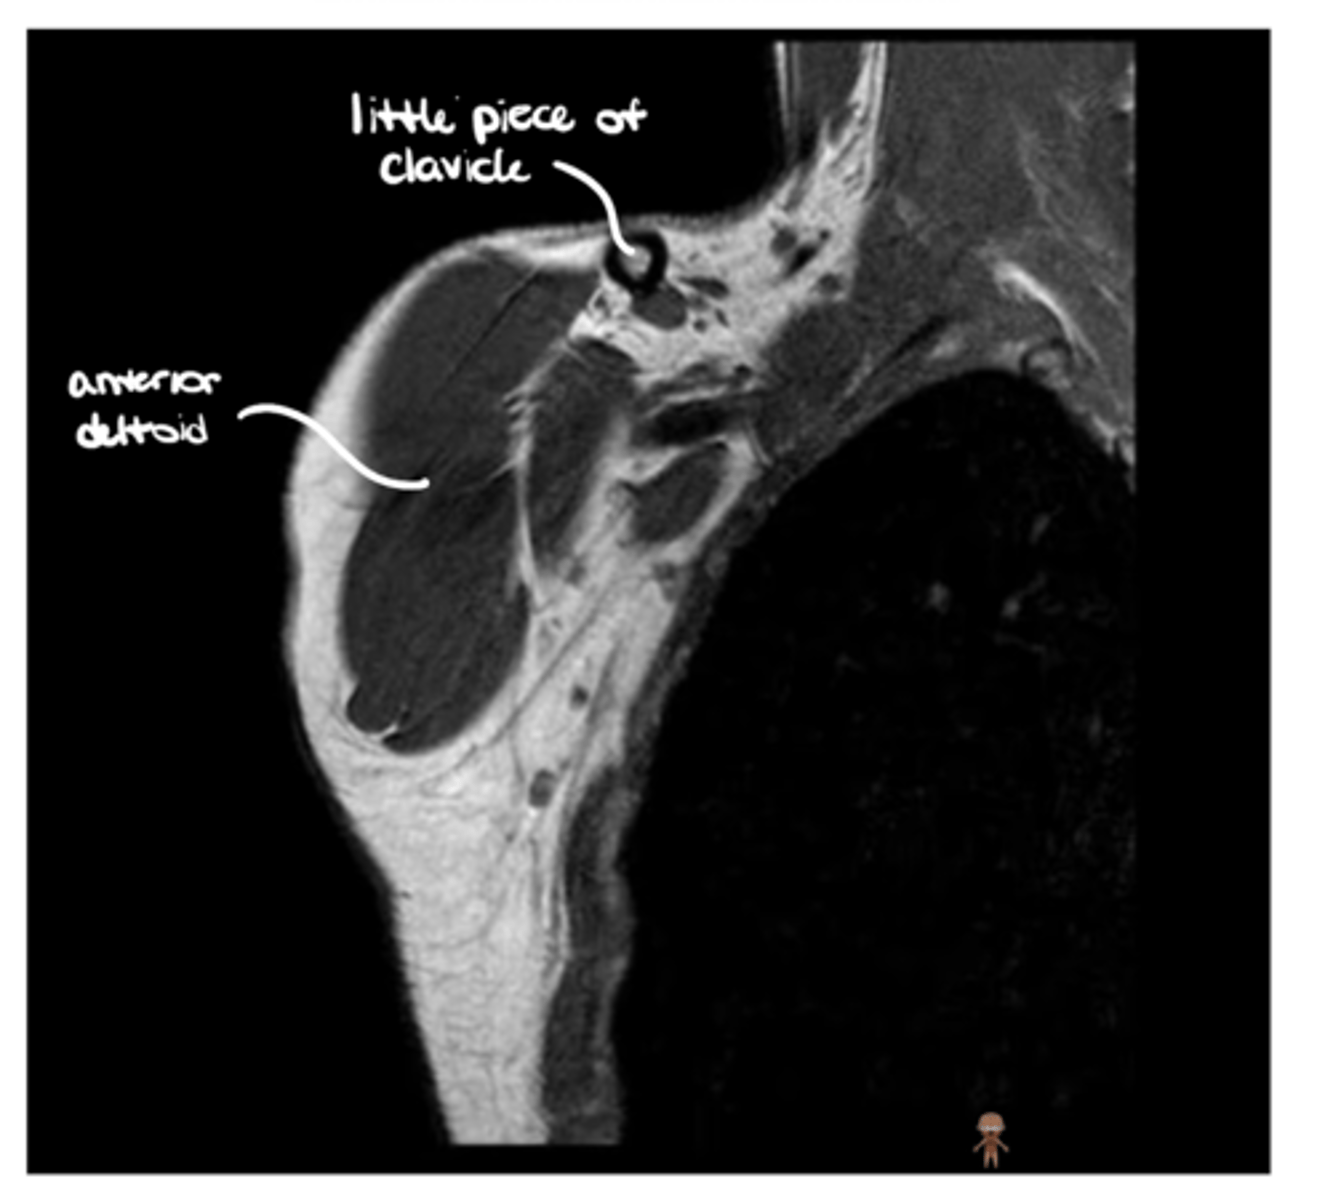

Anterior coronal view of the shoulder -- key to setting this image up is finding the coracoid process, which is NOT present on the back side

What type of view is this? Anterior vs. posterior? How do you know?

1. Anterior

2. Coracoid

1. What view is this image?

2. Which structure is being pointed to?